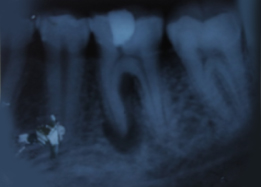

Pre-OP IOPAR